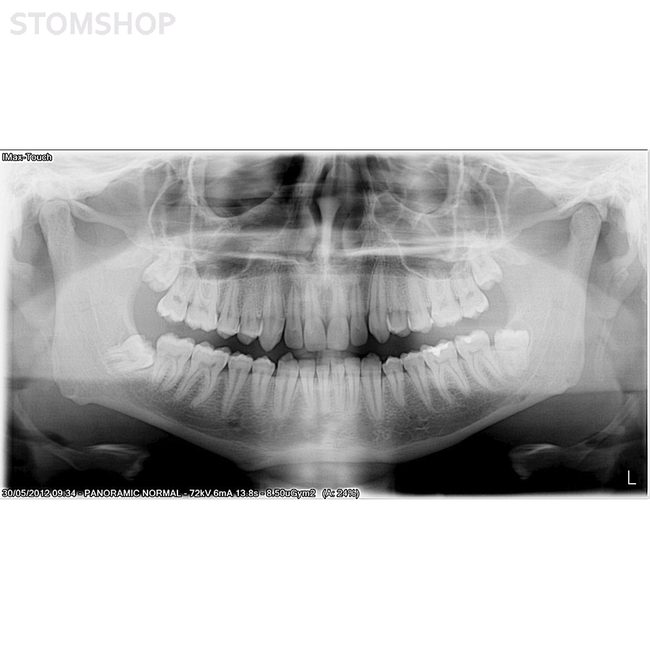

Ортопантомограф I-Max Touch Pano предназначен для получения панорамных снимков челюстей у взрослых и детей. Вывод изображения осуществляется на монитор, экран пульта и на флеш-карту. Значительное уменьшение дозы рентгеновского излучения. Полностью компьютеризированное управление. Без цефалостата.